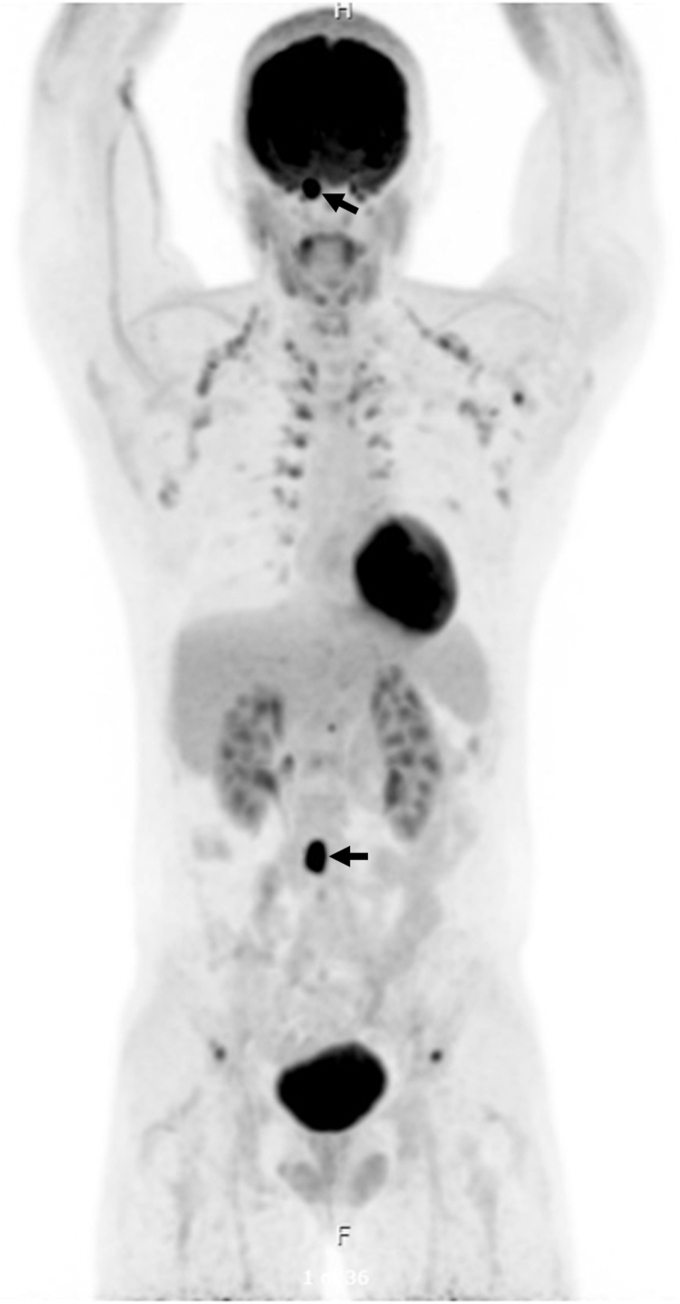

Our patient was a 31-year-old man diagnosed with periaortic PGL and succinate dehydrogenase subunit B pathogenic variant at the age of 9 years with cardiac arrest. He developed intra-abdominal and skeletal metastatic disease by the age of 14 years and treated with surgery, chemotherapy, and radiation. After being lost to follow-up, the patient presented emergently with headache, palpitations, hypertensive crisis, type 2 non-ST-elevation myocardial infarction, and catecholamine-induced cardiomyopathy, with plasma free metanephrine level of 61.0 pg/mL (0.0-88.0 pg/mL) and elevated serum free normetanephrine level of 662.9 pg/mL (0.0-210.1 pg/mL). Imaging showed a right frontal calvarial lesion, with 4.9-cm intracranial dural and 4.9-cm extracranial components, and a 1.5-cm occipital bone lesion. Following adrenergic blockade, the patient underwent resection of the frontal lesion with pathology showing metastatic PGL.

A multidisciplinary team was consulted. Because of potential neurotoxicity, radiology advised against radiotherapy. Oncology advised monitoring. Seven months postoperatively, gallium-68 dodecane tetraacetic acid–octreotate positron emission tomography/computed tomography showed no recurrence at the surgical site, stable occipital lesion, and additional skeletal metastases. The patient is planned for peptide receptor radionuclide therapy.